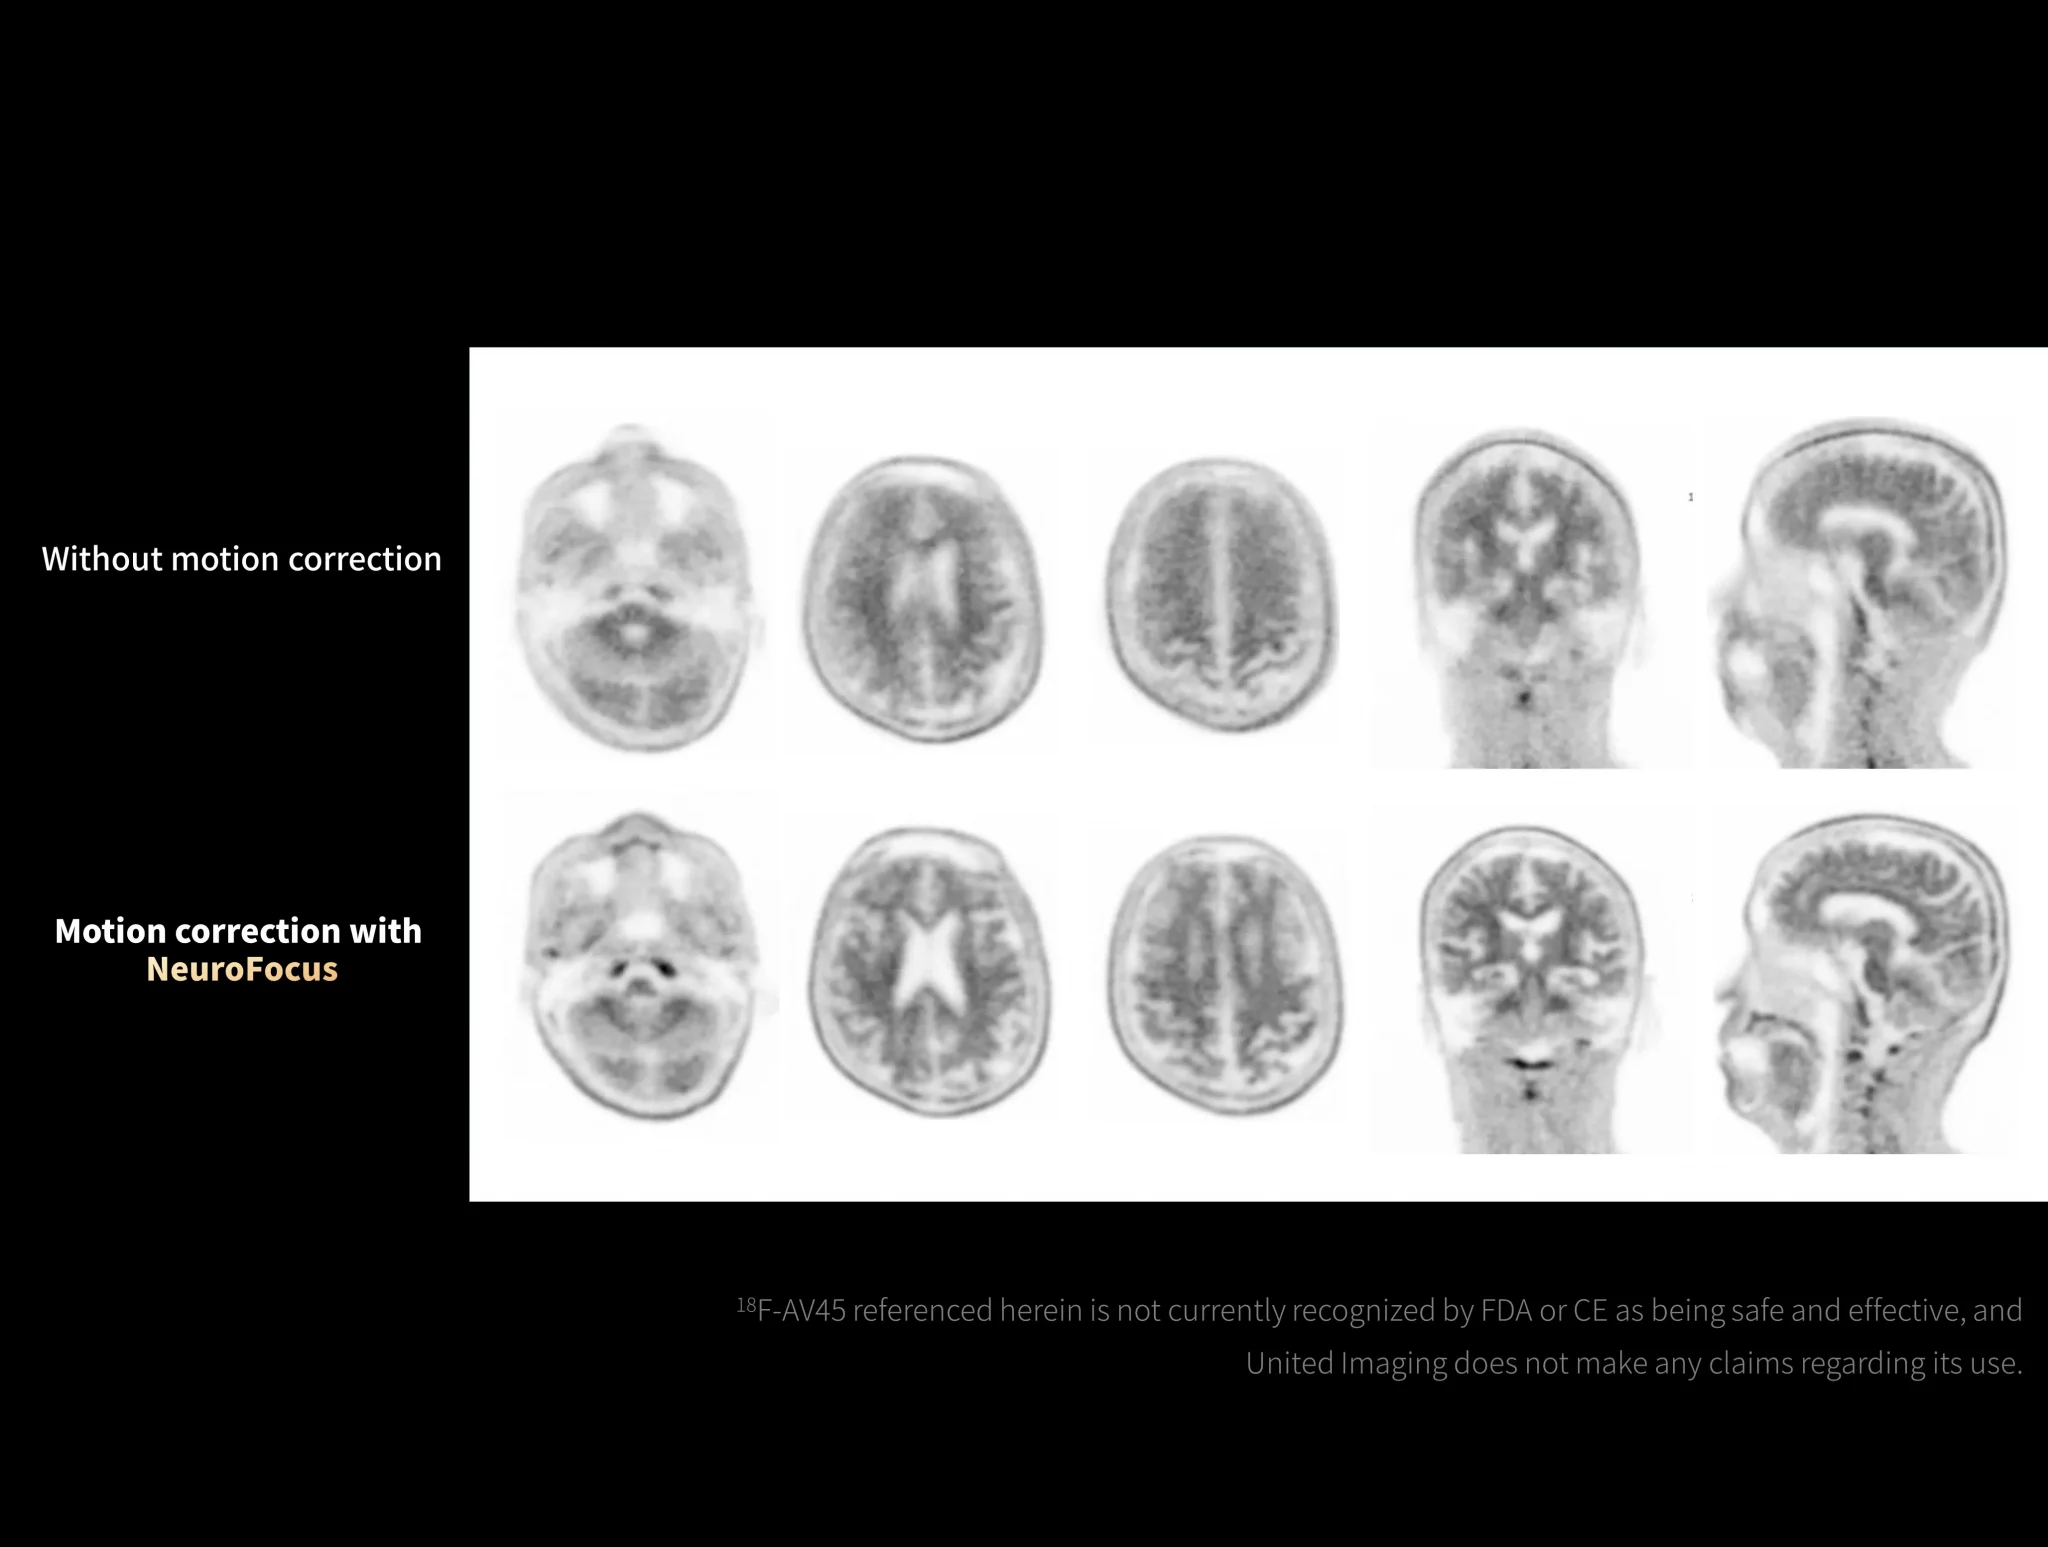

uMI Panorama is greatly empowered by innovative technologies integrated into the uExcel SCAN and uExcel CARE workflows. With uExcel SCAN, you can rely on intelligent positioning, scanning, and motion correction to streamline your routine tasks and maximinze your work efficiency. And uExcel CARE features uExcel DPR and uExcel AIIR reconstruction algorithms to ensure clear images even at low doses.